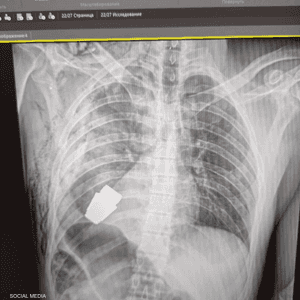

والأمر بحاجة إلى صور الأشعة الصحيحة، والأدوات الصحية، وهذا الأمر يمكن أن يكون تحديا وليس دائما سهلا، وفق الجراح الأميركي.